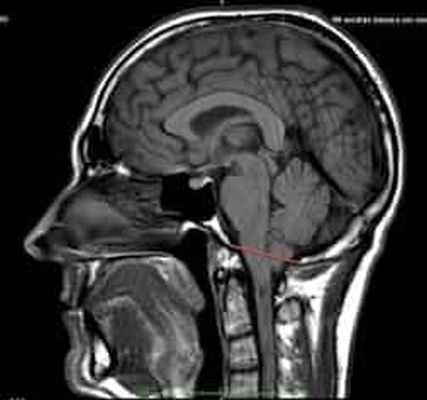

МР-картина ААК II типа – четко визуализируется каудальное смещении нижних отделов червя мозжечка,

продолговатого мозга, а также гидроцефалия